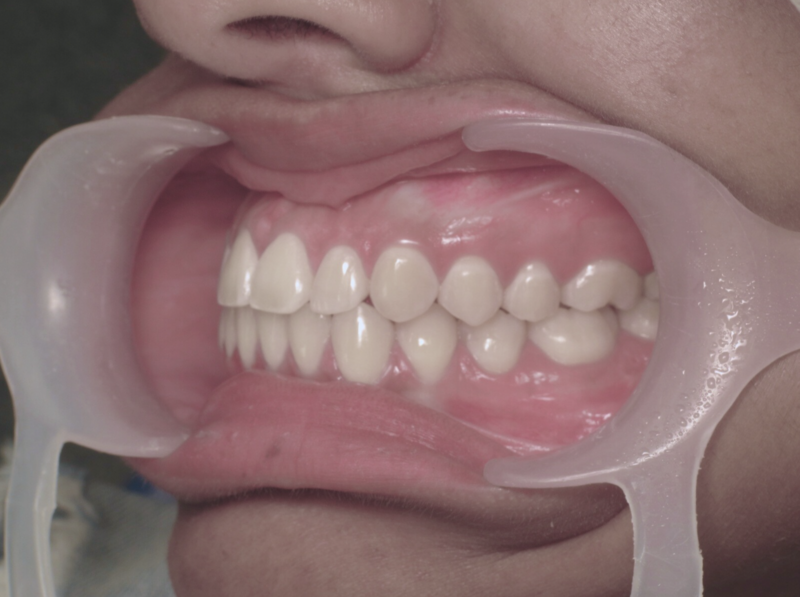

Cas n°2 traité par aligneurs - adolescent

Ce cas d'une adolescente illustre la puissance des aligneurs dans la correction d'une Classe II sévère sans extraction. La stratégie a reposé sur une distalisation séquentielle de l'arcade supérieure, soutenue par une coopération soutenue du port d'élastiques intermaxillaires.

Cette approche a permis d'annuler un surplomb incisif (overjet) important tout en réhabilitant une occlusion de Classe I stable. L'absence d'extraction a été déterminante pour préserver l'harmonie du profil, évitant le creusement du visage souvent lié aux traitements soustractifs classiques.

Résultats clés :

• Conservation dentaire : Alignement total sans perte de prémolaires.

• Fonctionnalité : Engrènement parfait et stable.

• Esthétique faciale : Soutien labial optimal et sourire élargi.

C'est une démonstration claire de l'orthodontie moderne : efficace, esthétique et respectueuse de l'anatomie naturelle.

Avant

Après